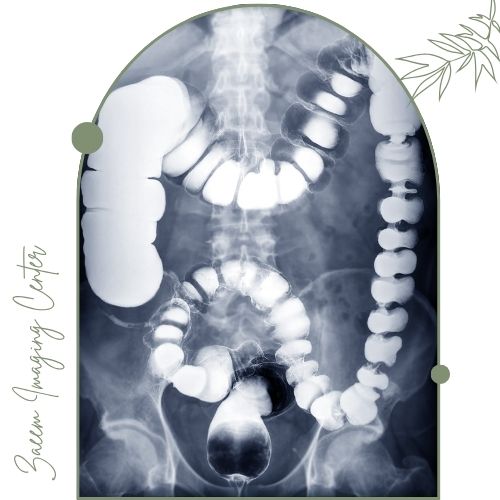

Barium Enema یکی از روش‌های تصویربرداری تخصصی و غیرتهاجمی است که برای بررسی وضعیت روده بزرگ (کولون) و راست‌روده (رکتوم) استفاده می‌شود. در این روش ماده حاجب باریم سولفات از طریق مقعد وارد روده بزرگ می‌شود تا دیواره داخلی روده به‌صورت واضح در تصاویر اشعه ایکس دیده شود. این تکنیک به تشخیص بسیاری از بیماری‌های روده‌ای کمک می‌کند از جمله پولیپ‌ها، تومورها، بیماری‌های التهابی، تنگی و انسداد روده و حتی وجود زخم یا آسیب در مخاط.

باریم انما یا عکس رنگی روده یکی از دقیق‌ترین روش‌های تصویربرداری غیرتهاجمی گوارشی است که با استفاده از ماده حاجب باریم و دستگاه‌های پیشرفته امکان بررسی کامل روده بزرگ و تشخیص بیماری‌هایی مانند پولیپ، تومور، التهاب و انسداد روده را فراهم می‌کند. این روش با آمادگی مناسب قبل از تصویربرداری و مراقبت‌های ساده بعد از آن معمولا بدون درد و نیاز به بستری انجام می‌شود. بهترین گزینه برای انجام باریم انما در کرج مرکز تصویربرداری زعیم است که با مدیریت متخصصین شناخته‌ شده، به‌کارگیری فناوری‌های مدرن و ارائه خدمات تحت پوشش بیمه محیطی امن، دقیق و سریع را برای بیماران فراهم می‌کند. در این مرکز انتخابی مطمئن برای سلامت دستگاه گوارش، گزارش‌های تخصصی و قابل فهم در کوتاه‌ترین زمان و با کیفیت عالی در اختیار مراجعین قرار می‌گیرد.